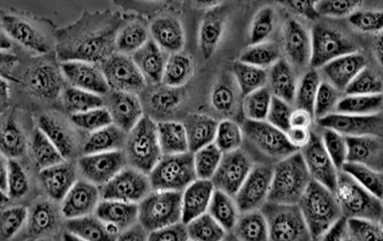

Before-After: Levend Bloed Analyse – Van Rouleaux-Vorming naar Vrije Stroom

Links: Bloed na 10 minuten bellen zonder bescherming – duidelijke klontering (rouleaux), wat zuurstoftransport belemmert en vermoeidheid veroorzaakt. Rechts: Na harmonisatie met MemonizerCOMBI – soepele doorbloeding, optimale zuurstofopname. Wetenschappelijk bewezen: Meer energie, minder ontstekingen.